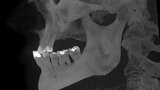

Implantacja z wykorzystaniem szablonu nawigacyjnego 3D